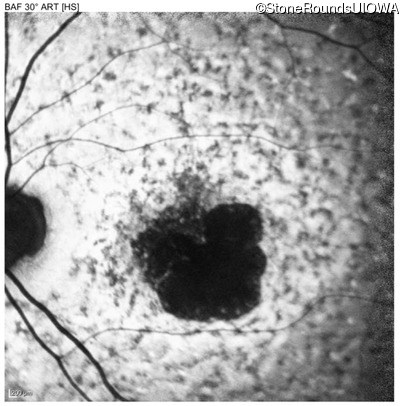

All three of the cardinal ophthalmic features of Mendelian macular dystrophies are present in this patient. The most striking features of the fundus exam are the numerous yellow flecks at the level of the RPE. Flecks are most commonly seen in AR Stargardt disease and pattern dystrophy although they may be seen in some of the rarer Mendelian maculopathies as well. The visual acuity in patients with AR Stargardt disease is often "worse than the fundus looks" while the acuity in pattern dystrophy is often quite good despite extensive flecks. The pedigree of this patient is compatible with ABCA4-associated Stargardt disease and the better than expected acuity is attributable to foveal sparing (see below). The onset of reduced acuity at age 10 is much more characteristic of ABCA4 disease than pattern dystrophy. Another feature present in this patient that is very frequently seen in Stargardt disease is peripapillary sparing. However, this sign can be seen in pattern dystrophy as well. When central atrophy is present in ABCA4-associated Stargardt disease it often somewhat shiny (which is uncommon with the geographic atrophy of pattern dystrophy or age-related macular degeneration). Some patients with ABCA4-associated Stargardt disease can have some preservation of the fovea giving a zonal "bullseye" appearance to the center of the macula. Sometimes this preservation is associated with preserved acuity as in this case. The outer nuclear layer (ONL) is much thinner than normal on OCT, indicative of photoreceptor loss. This is associated with a thinning of the ellipsoid zone which is usually many times brighter and thicker than the external limiting membrane (ELM). These two lines are essentially equal in intensity in this patient. The foveal sparing is seen on OCT only as a small bit of retinal convexity in the center of the atrophy coupled with a small bit of residual RPE flanked by bare Bruch's membrane. The presence of a robust I2e isopter on Goldmann perimetry places this patient in the least severe half of all Stargardt patients (see Schindler, et al., 2010). Most patients with ABCA4-associated disease are somewhat myopic as is this patient. Stargardt patients also tend to perform very poorly on pseudoisochromatic plates, even when their acuity is still fairly good as it is here.